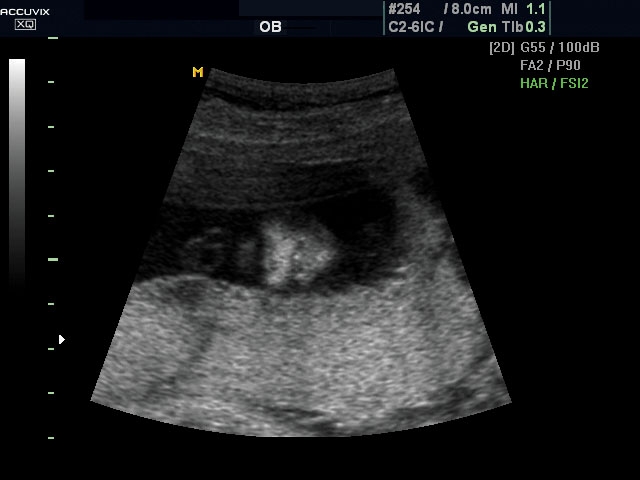

Magzati koponya képe normál 2D módbanMagzati koponya 2D képe bekapcsolt Dynamic MR funkcióvalMagzat törzsének képe normál 2D módbanMagzat törzsének képe bekapcsolt Dynamic MR funkcióvalMagzat felsőajakjának és orrának képeMagzat felsőajakjának és orrának képe bekapcsolt Dynamic MR funkcióval

A pontos analízis és diagnózis iránti egyre növekvő igény kiszolgálására a MEDISON egy új real time képfeldolgozó technológiát fejlesztett ki Dynamic MR™ elnevezéssel. Az eljárás a diagnosztikus ismeretanyagot a precizitás és a pontosság egy teljesen új szintjére emeli. Használata az alapvető 2D ultrahang képinformáció real time, kivételesen kristálytiszta és kiemelkedően részletezett megjelenítését teszi lehetővé tűéles kontúrok és finoman rajzolt szövetstruktúra mellett. A DMR™  technológia ideális eszköze az ultrahang-diagnosztikának kezdve a szülészet-nőgyógyászattól a foetalis echon át az általános alkalmazásokig.